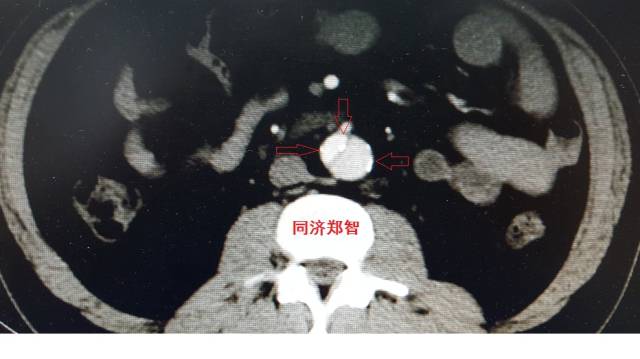

病例十

腹主动脉平扫CT提示正常外周一圈的钙化影中有内移的钙化影(红色箭头所示),CTA 证实为腹主动脉夹层。